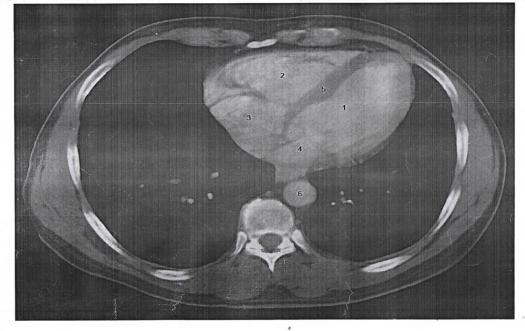

1. The part number 6 represents:

Explanation

The correct answer is descending thoracic aorta. This is because the descending thoracic aorta refers to the part of the aorta that extends downward from the arch of the aorta, through the thoracic cavity, and into the abdominal cavity. It carries oxygenated blood from the heart to the lower parts of the body. The other options, ascending thoracic aorta, pulmonary artery, and arch of the aorta, do not accurately represent part number 6.

8. The part number 3 represents:

The correct answer is Tracheal shadow. In the given options, the part number 3 represents the tracheal shadow. The trachea is a tube-like structure that carries air to and from the lungs. It appears as a dark shadow on imaging studies such as X-rays. Therefore, option 3 is the correct representation of part number 3.